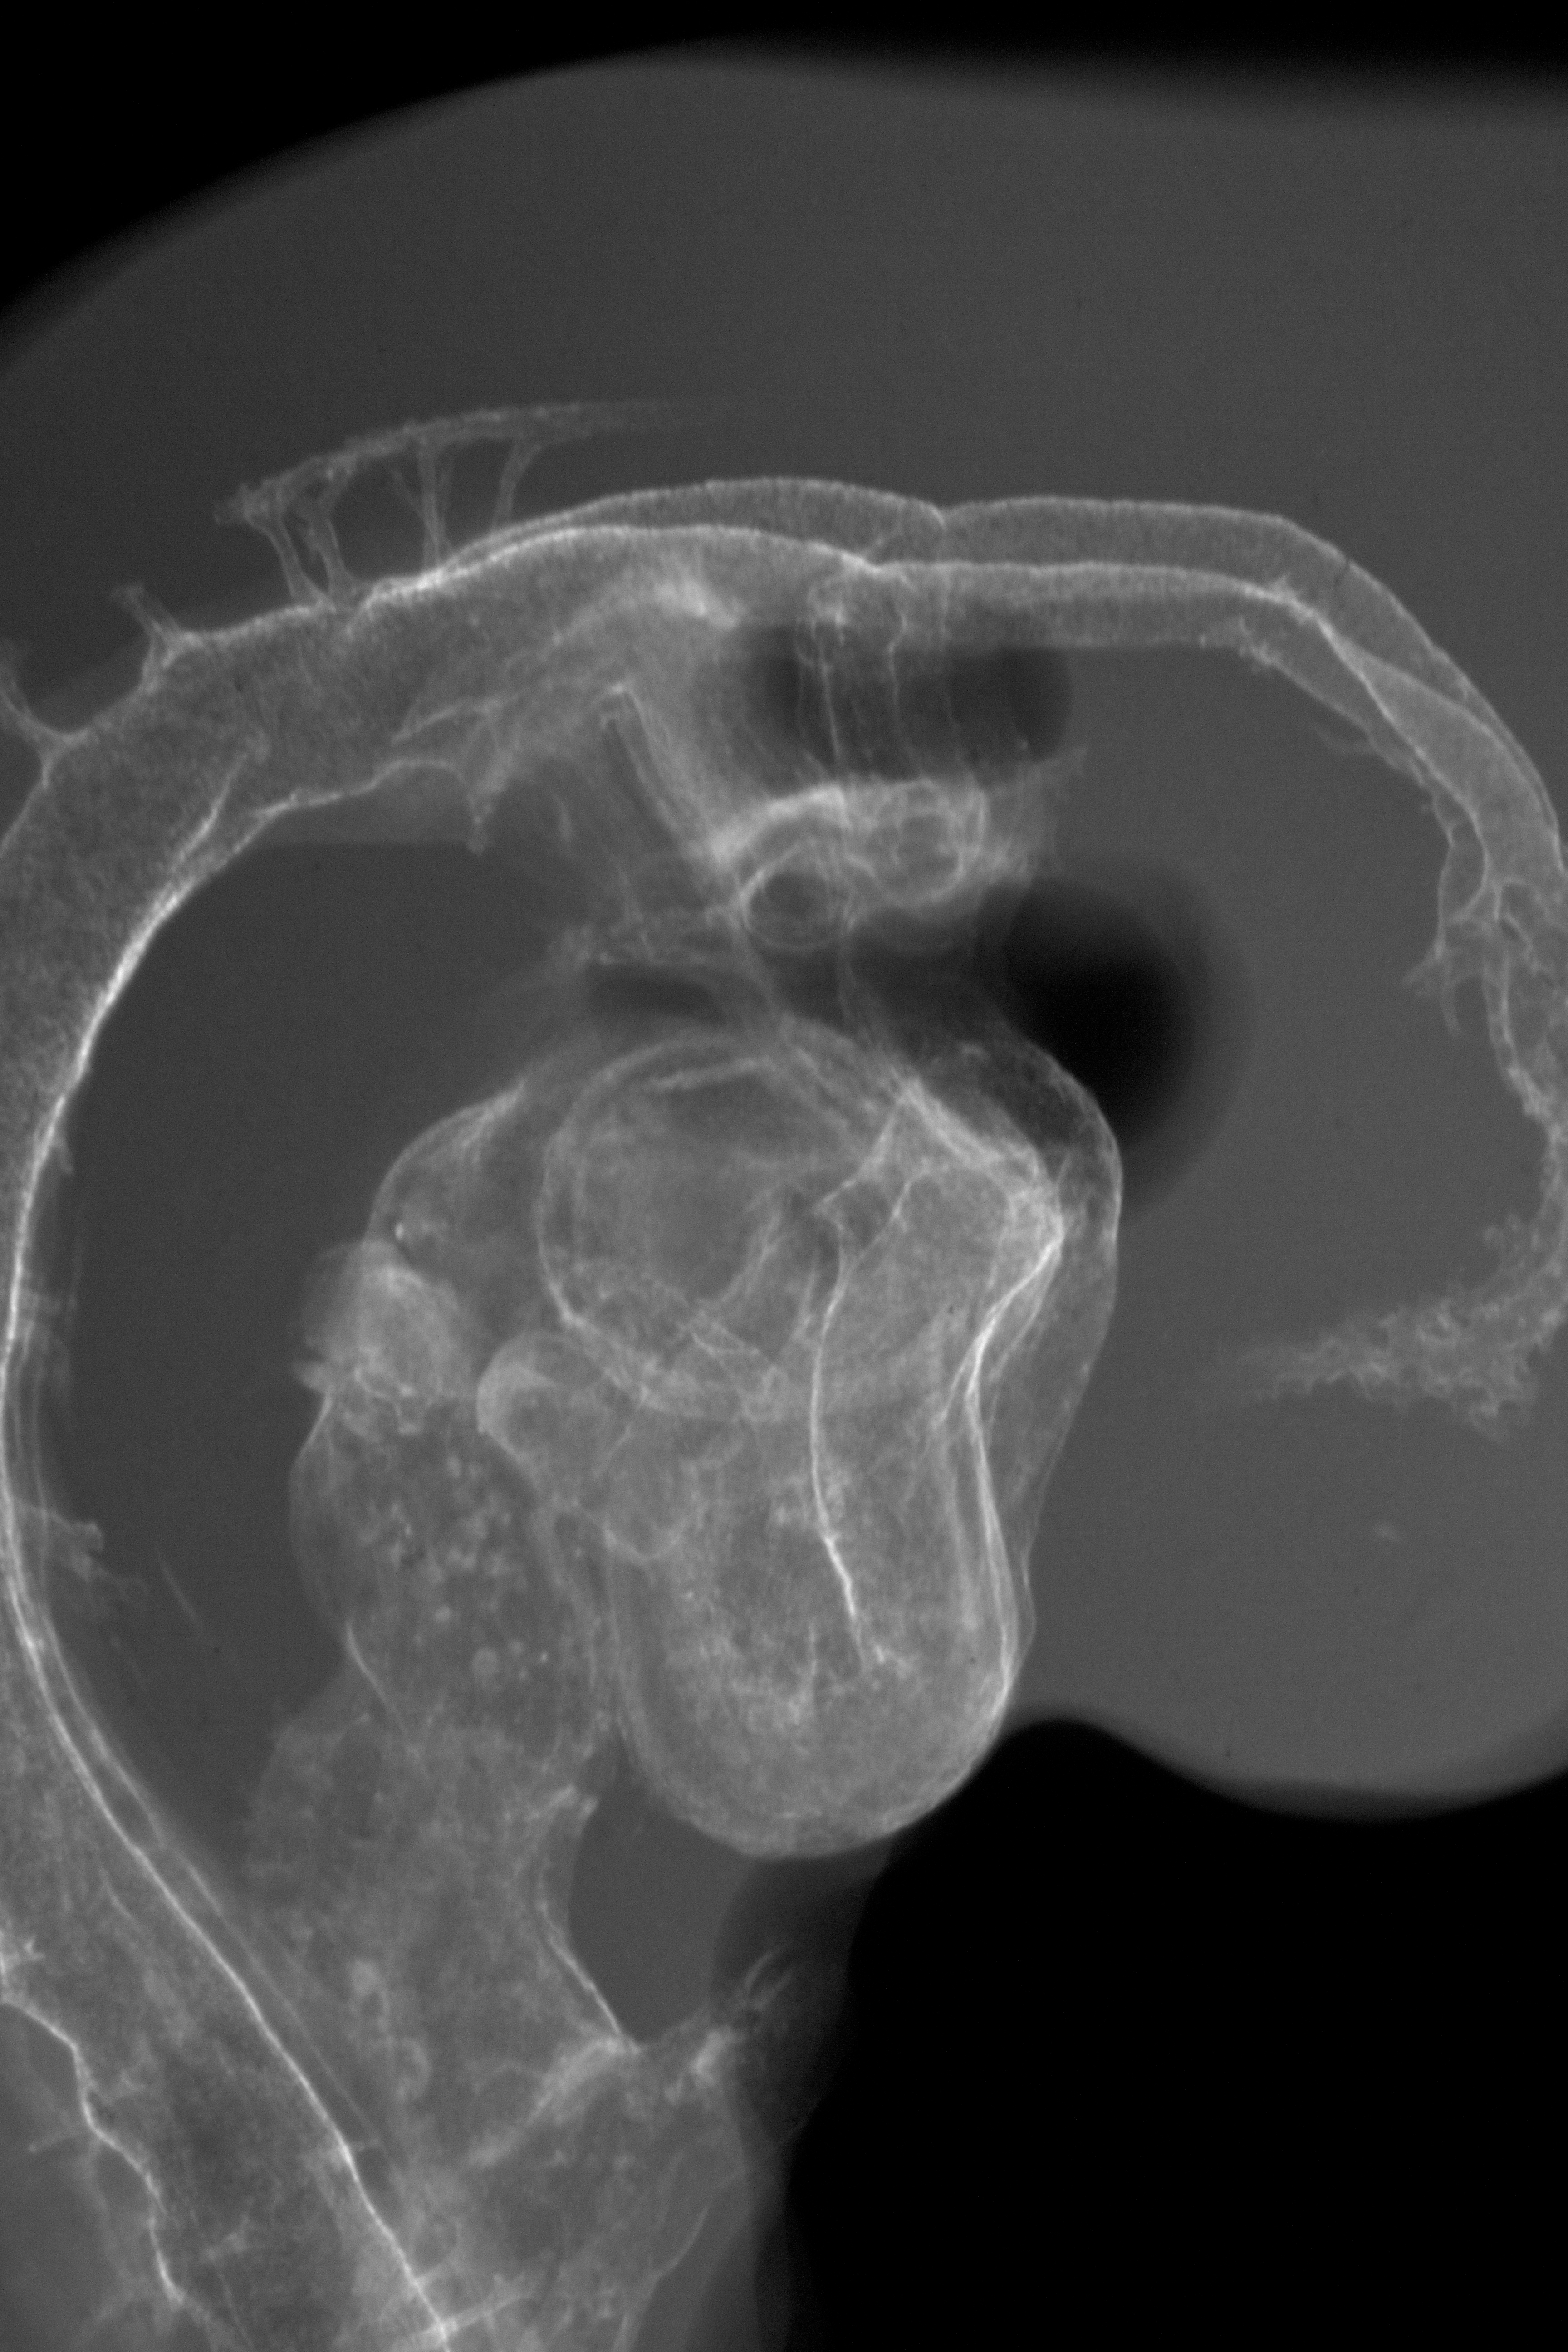

Chick Embryo Microangiography

Hamburger-Hamilton (HH) Stage 19 (approx. 3 - 3.5 days)

X-Ray Micrographs